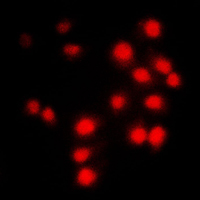

Immunofluorescent analysis of Cyclin A1/2 staining in NIH3T3 cells. Formalin-fixed cells were permeabilized with 0.1% Triton X-100 in TBS for 5-10 minutes and blocked with 3% BSA-PBS for 30 minutes at room temperature. Cells were probed with the primary antibody in 3% BSA-PBS and incubated overnight at 4 °C in a humidified chamber. Cells were washed with PBST and incubated with a DyLight 594-conjugated secondary antibody (red) in PBS at room temperature in the dark.